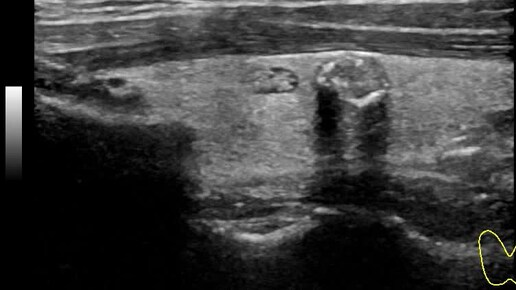

Видео к статье "Стратификация узлов щитовидной железы. TI-RADS-4" https://dzen.ru/a/ZwNx-uQp-Sfk6L46

Ультразвуковые находки от врача УЗД Зорина Я.П.